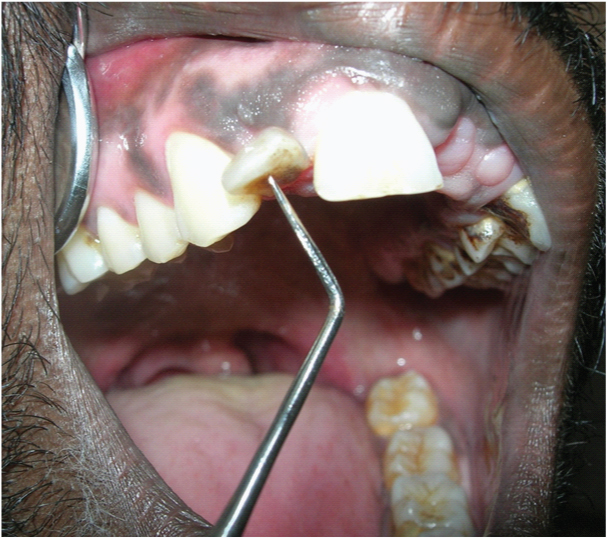

A 28-year-old male patient reported to the Department of Oral Medicine and Radiology, Saveetha University (Chennai, India) with a chief complaint of mobility of teeth in upper and lower jaw and gingival enlargement for past two months. He gave history of loss of front teeth in both jaws and gradual enlargement of gingival since then. [Table/Fig-1] showing the partially edentulous maxilla and mandible along with the gingival enlargement. [Table/Fig-2] showing the extent of mobility of 12.

Showing the extent of mobility of 12